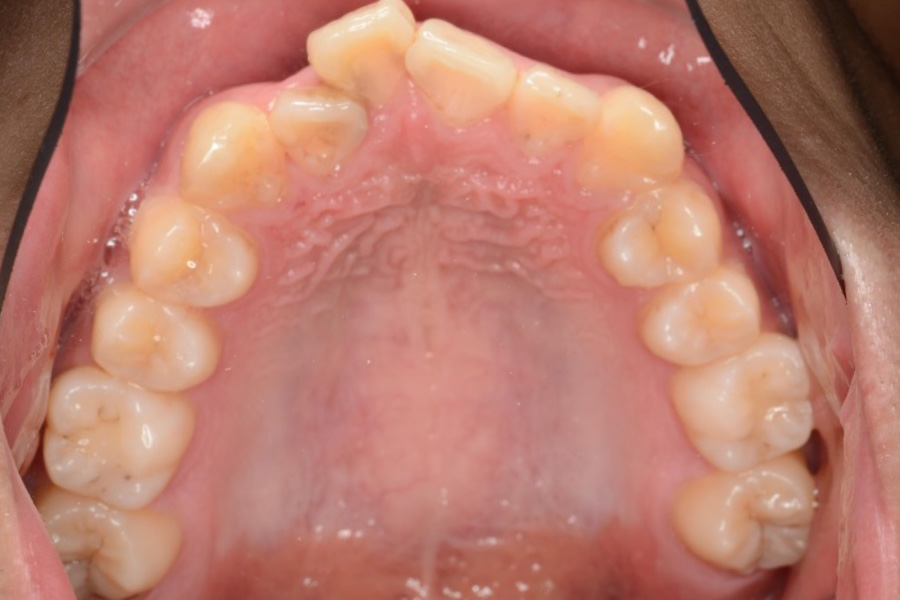

治療後

治療内容 インビザライン矯正

非抜歯